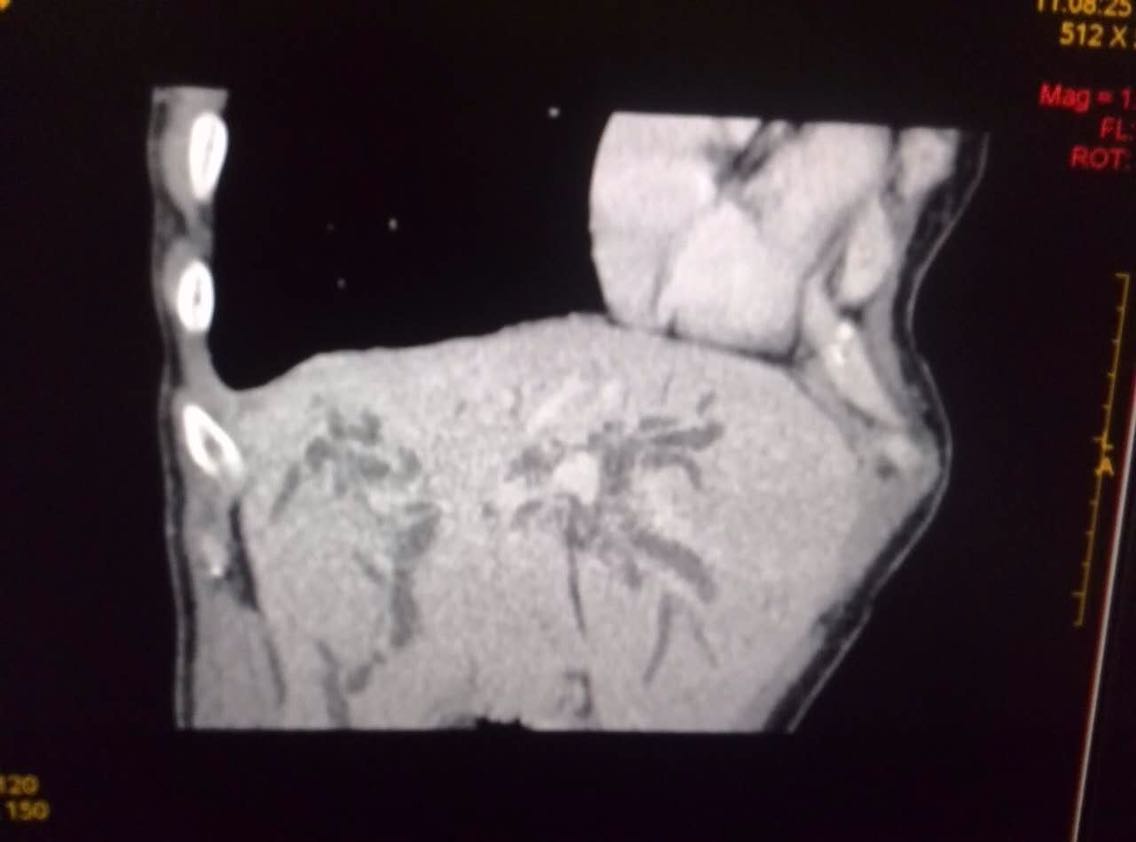

生命体征平稳,全身皮肤巩膜黄染,恶病质,腹部臌胀,全腹软,肝脏区扣痛,移动性浊音阳性。 CT提示:肝门胆管癌